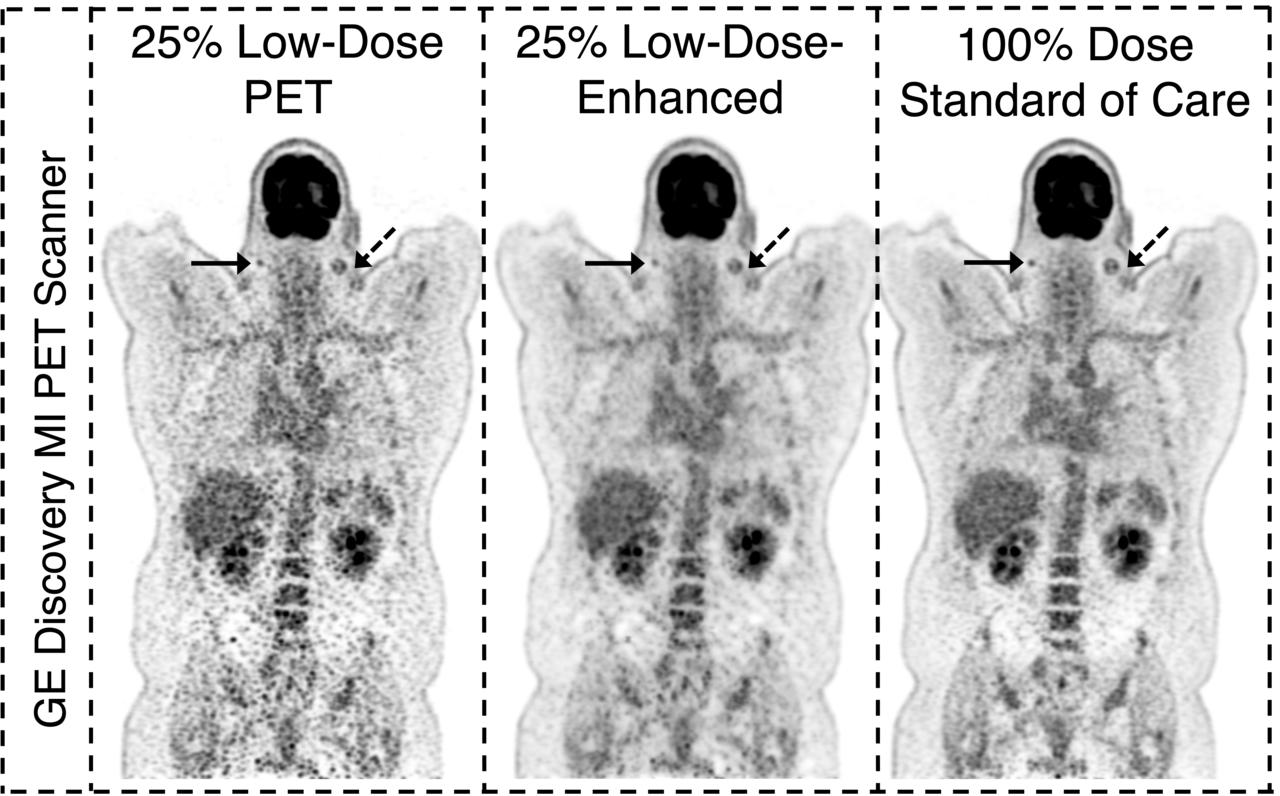

An example image of subjects scanned on three different PET scanners with body mass index (BMI) of over 30 is shown below. Traditionally, PET scans are sensitive to varying body habitus and suffer from low signal-to-noise ratio in subjects with higher BMI. We demonstrate how our method improves the diagnostic image quality of low-count PET scans even in high BMI patients.